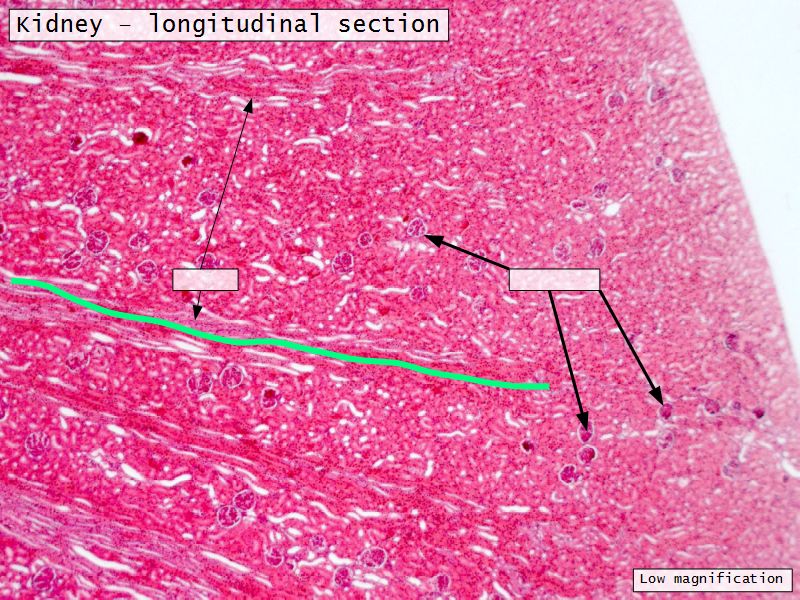

Appearance

- Cortex

- Renal corpuscles

- Convoluted tubules

- Medulla

- Loops of Henle

- Collecting tubules

Kidney lobule

- Group of neprons

- Open into branches

- Same collecting duct

- Not clearly demarcated

- Interlobular arteries/veins